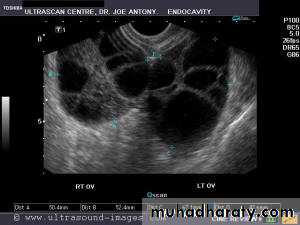

• Ovarian hyperstimulation syndrome (OHSS):

Transvaginal ultrasound images of ovarian hyperstimulation syndrome:This young adult female patient showed multiple large theca lutein cysts of both ovaries, arranged in spoke-wheel pattern (ultrasound images above) which were the result of use of gonadotropins in the management of infertility. The cysts vary in size from 2 to 4 cms. with the ovaries massively enlarged (each ovary measures up to 7 cms. in size). This can be classified as grade-2 hyperstimulation of the ovaries (ovarian diameter from 5 to 10 cms.). There is not evidence of ascites. The color Doppler image of the ovaries shows vessels passing along the margins of the cysts. One of the complications of such enlarged ovaries in OHSS is torsion and in certain cases rupture of the ovaries, both of which are medical emergencies. Ovarian hyperstimulation syndrome is known to occur more frequently in patients of pre-existing Polycystic ovaries (PCO).